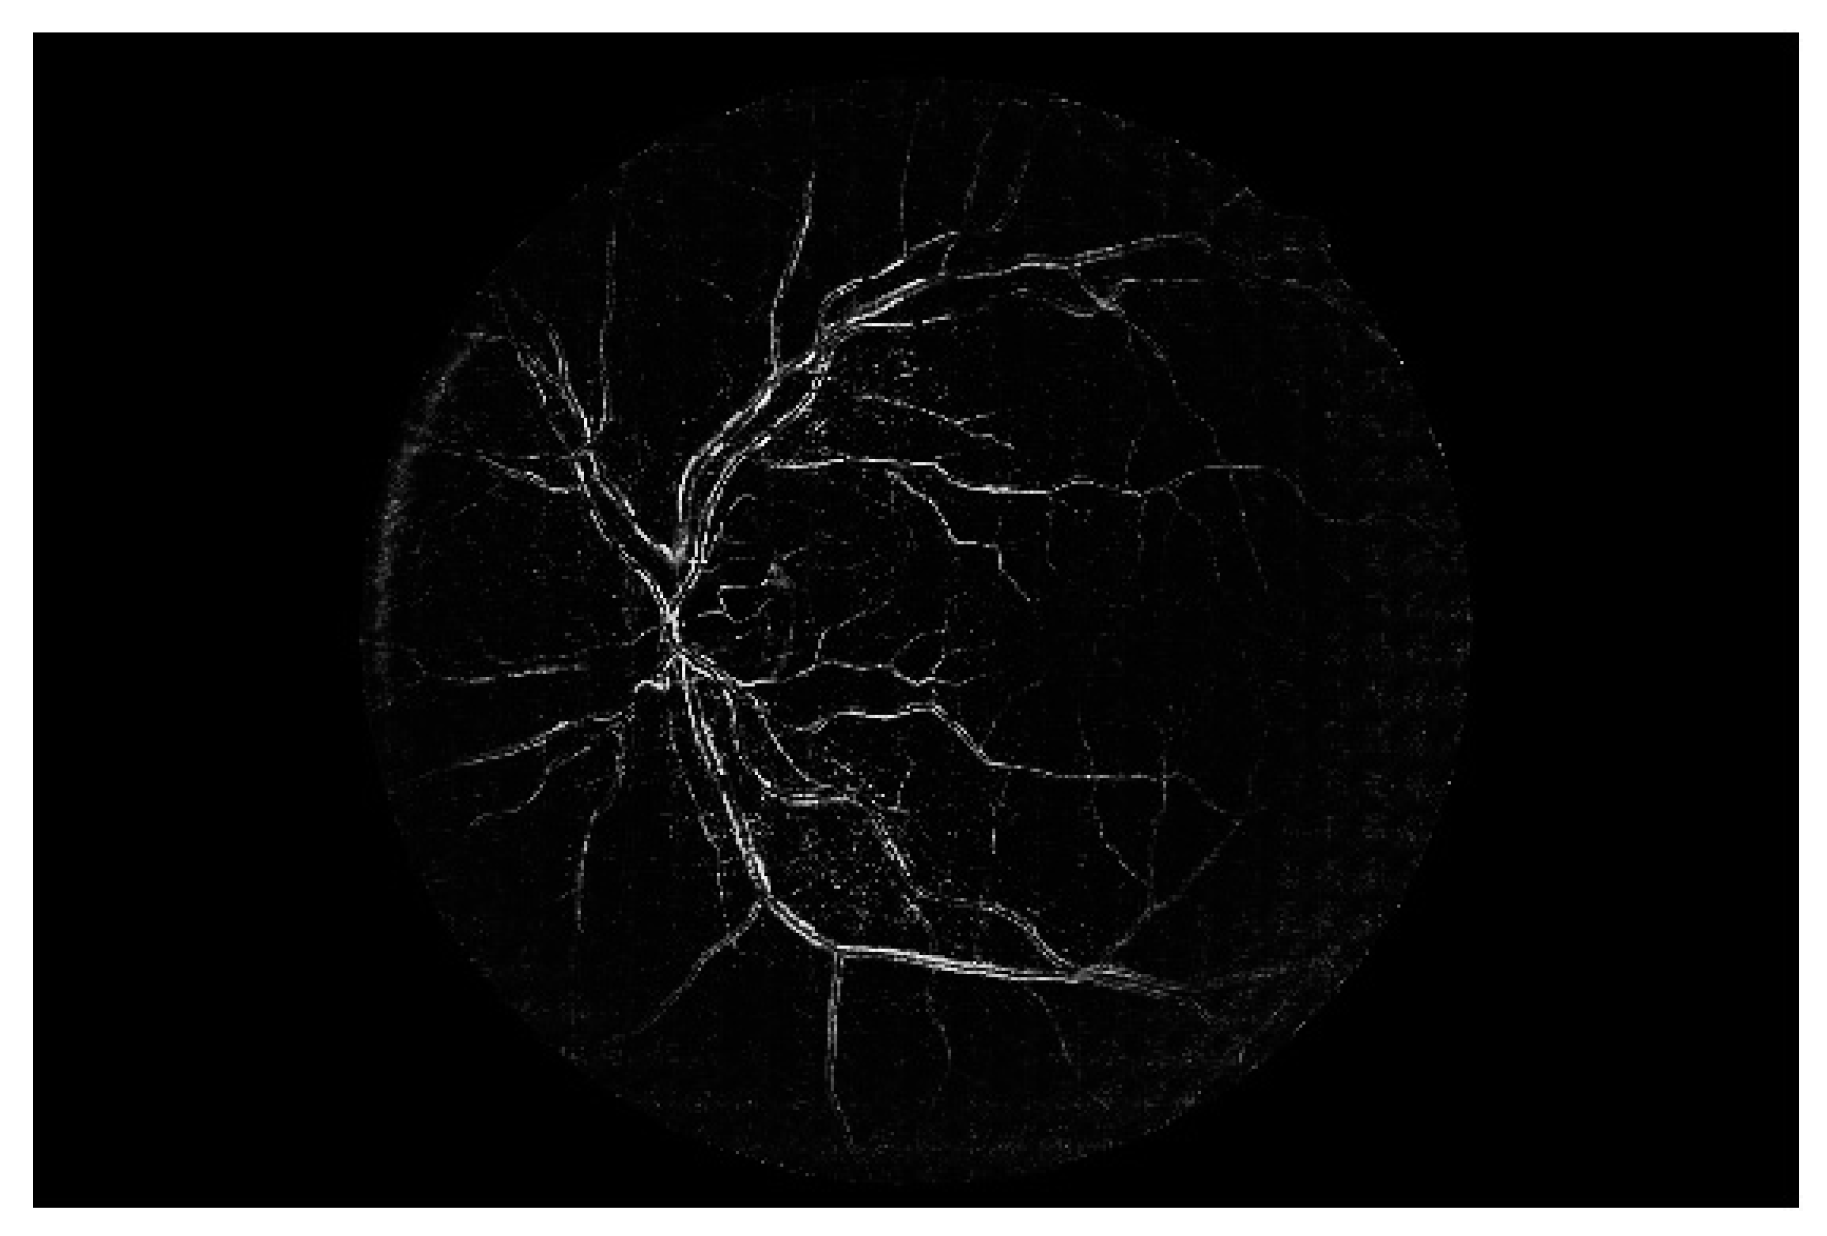

Figure 7 shows a simple example of the MLP method used in this study. The high-resolution fundus (HRF) [74] image dataset contains higher-quality retinal images compared to those of DRIVE, and provides both low- and high-quality retinal images. Figure 8 shows a low-quality retinal image. The bottom part of the image is unclear owing to white noise caused by environmental factors. Figure 9 shows a retinal vessel image created by performing vessel segmentation on Figure 8. The white noise seen in Figure 8 also affects vessel segmentation. Figure 10 is a high-quality retinal image and the white noise observed in Figure 8 has disappeared. The bottom part of the vessel stem is clearly visible, which did not appear in the original image. Figure 11 shows a retinal vessel image created by performing vessel segmentation on Figure 10. Unlike Figure 9, the bottom part of the vessel stem is shown clearly.

Figure 11. Retinal vessel image of Figure 10.